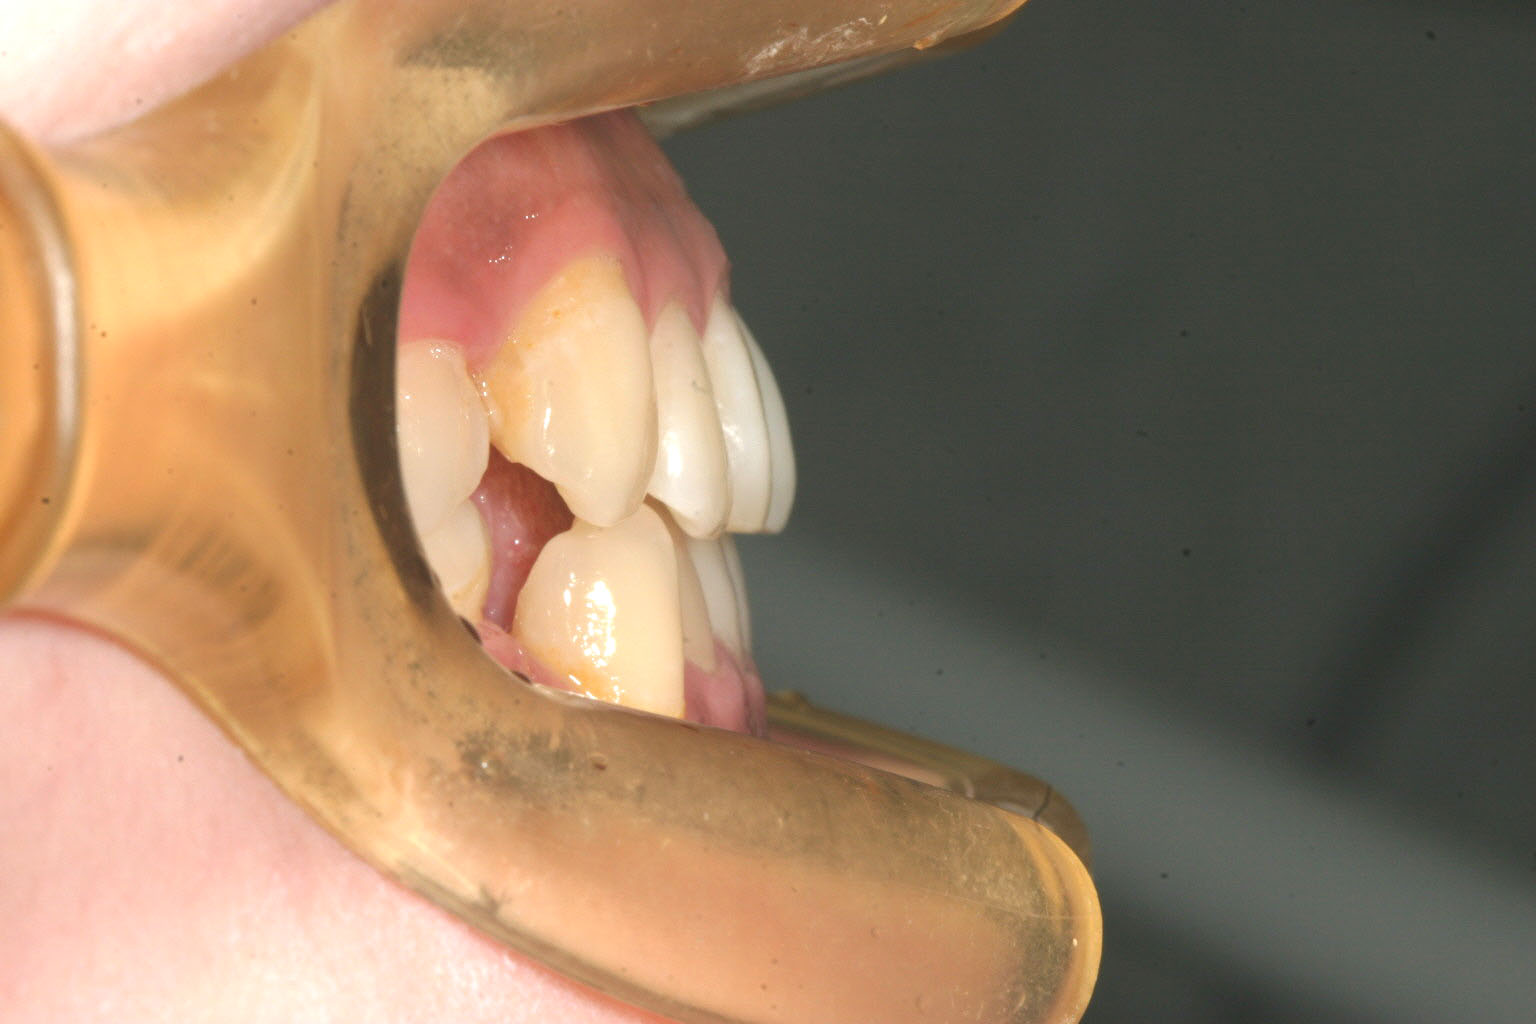

横から見た感じは顎を切りましたから、もうしゃくれ感は有りません。

側面感も綺麗な状態です。